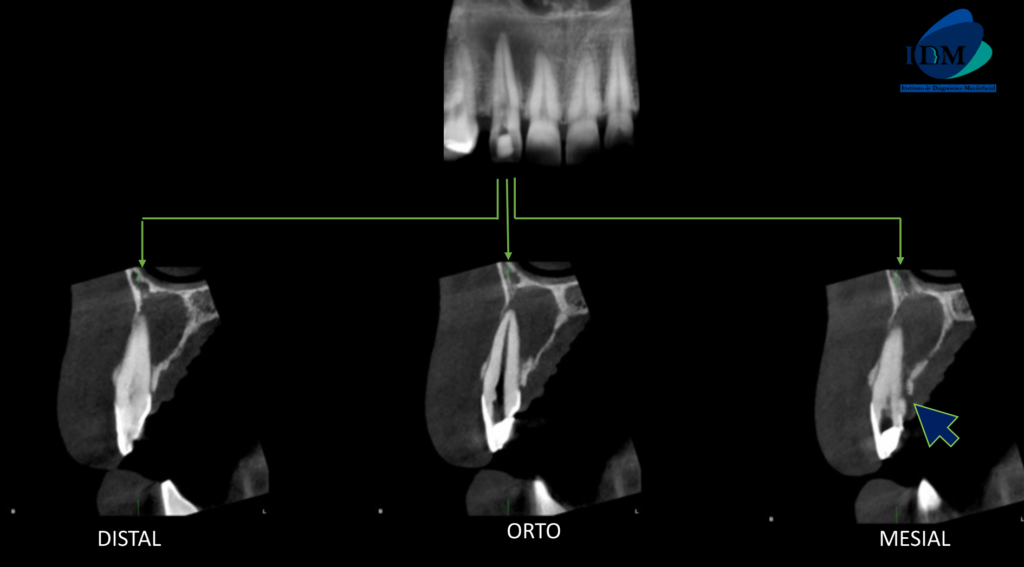

A la evaluación de la tomografía computarizada de campo reducido de la pieza 22 se observa (además de la restauración y la preparación endodontica parcial del conducto pulpar), una alteración de la morfología radicular caracterizada por la presencia de un surco palatino que va desde tercio cervical hasta el tercio apical y que ocasiona el ensanchamiento del espacio para el ligamento periodontal (vista en corte axial y transaxial), asimismo se observa la presencia de un proceso osteolítico periapical que ocasiona el adelgazamiento de las tablas óseas vestibular, palatina y del piso de fosa nasal de aparente origen endoperiodontal.

CORTES TRANSAXIALES